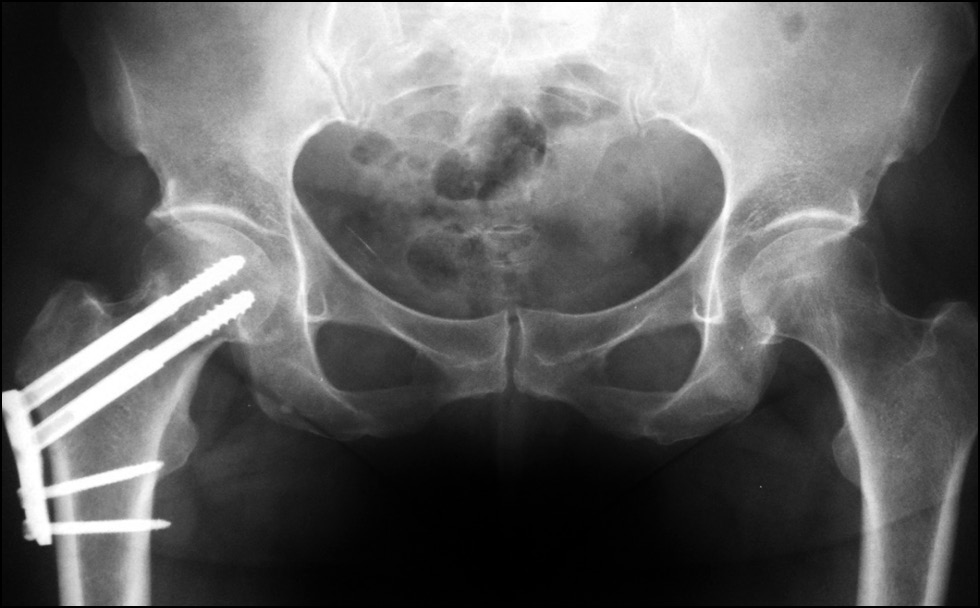

После удаления винта пациентка, несмотря на рекомендации дозирования нагрузки на оперированную конечность, продолжала ходить без дополнительной опоры. Через 6 месяцев с момента получения перелома ШБК при контрольной рентгенографии костей таза (рис. 8) обнаружена консолидация перелома. Пациентка ходит без дополнительной опоры и без хромоты, симптом Транделенбурга отрицательный. Оценка качества жизни пациентки, рассчитанная с использованием опросника SF-36, соответствовала хорошему функциональному результату (физический компонент здоровья — 28,5 балла, психологический — 29,1 балла). Показатель по шкале Харриса составил 90 баллов и был оценён как отличный функциональный результат.

Рис. 8. Рентгенография костей таза пациентки Н. через 6 месяцев с момента перелома шейки бедренной кости.

Fig. 8. X-ray of the pelvic bones of patient N. 6 months after the fracture of the femoral neck.